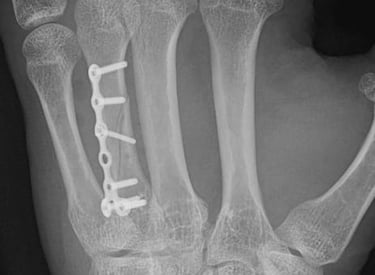

Artroscopia de muñeca

Cirugía mínimamente invasiva para la patología más compleja de la muñeca